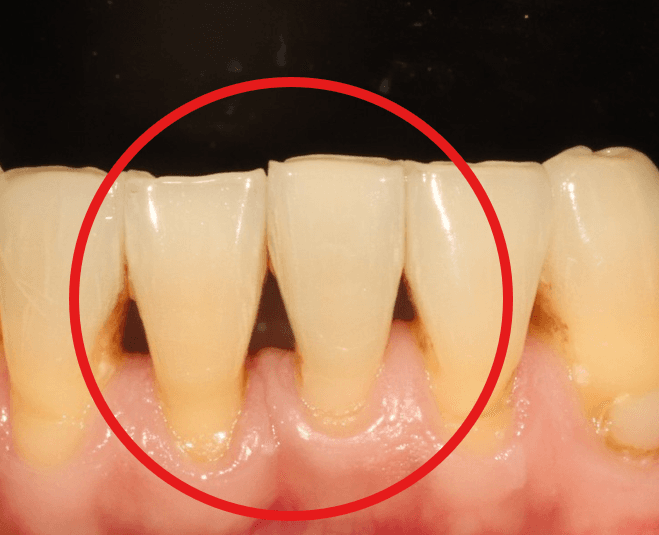

블랙 트라이앵글은 치아와 치아 사이, 잇몸이 채워야 할 공간에 빈틈이 생기면서 나타나는 검은 삼각형 모양의 공간을 말합니다.

웃을 때 눈에 띄기 때문에 심미적으로 스트레스를 받으시는 분들이 많고, 음식물이 끼기도 쉬워 구강 위생 관리에도 신경이 쓰이는 부분입니다.

1. 치주염(잇몸 질환)

가장 대표적인 원인은 치주염입니다.

치아는 머리(치관)와 뿌리(치근)로 나뉘는데, 건강한 상태라면 뿌리를 감싸는 잇몸뼈가 충분히 높이 차 있어서 치아 사이 틈이 거의 보이지 않습니다.

그런데 치석이 쌓이면 문제가 시작됩니다.

치석은 단순한 돌덩이가 아니라 세균의 군집입니다.

이 세균들이 내뿜는 독소가 잇몸에 염증을 일으키고, 시간이 지나면서 잇몸뼈가 서서히 녹아 내려가게 됩니다.

뼈가 많이 내려가면 치아가 흔들리기 시작하는데, 이것이 흔히 말하는 풍치입니다.

나이가 들수록 치주염 위험이 높아지고, 정기적인 스케일링과 잇몸 치료를 소홀히 하면 뼈 소실이 점점 진행됩니다.